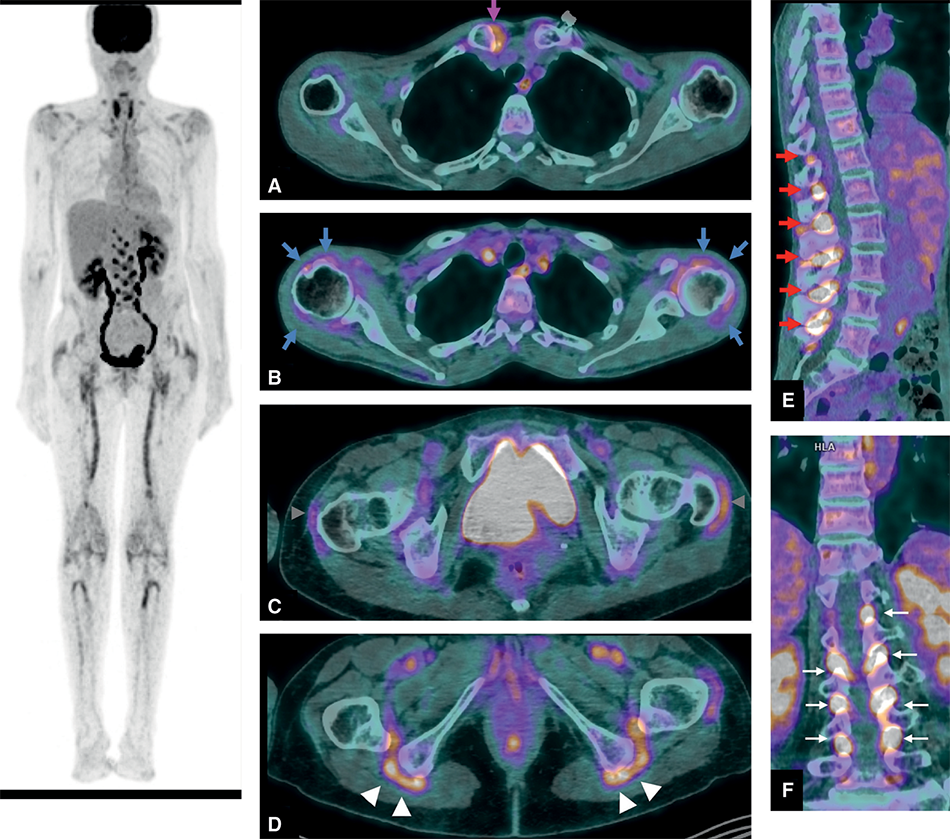

Fig. 16.4.

TEP-scan dans la PPR.

Hypermétabolismes articulaires et péri-articulaires intenses prédominant sur les ceintures et touchant notamment l’articulation acromioclaviculaire droite (A, flèche rose), péri-articulaires des deux épaules (B, flèches bleues), des enthèses sur les grands trochanters (C, têtes de flèches grises) et les tubérosités ischiatiques (D, têtes de flèches blanches) ainsi que des es- paces interépineux (E et F, flèches rouges et blanches). À noter : un hypermétabolisme des artères fémorales, évocateur d’artérite à cellules géantes associée (astérisque).

Cet examen avec un marquage au 18-fluorodésoxyglucose (18FDG) permet de visualiser les zones métaboliquement actives consommant du glucose.

Il existe dans la PPR des fixations très importantes et bilatérales (même sur les sites asymptomatiques cliniquement) (fig. 16.4) :

Du fait de son coût, de son caractère irradiant et en accord avec les recommandations pour la prise en charge de la pseudopolyarthrite rhizomélique de la Société française de rhumatologie, cet examen doit être réservé à une prescription ciblée en cas de doute diagnostique.